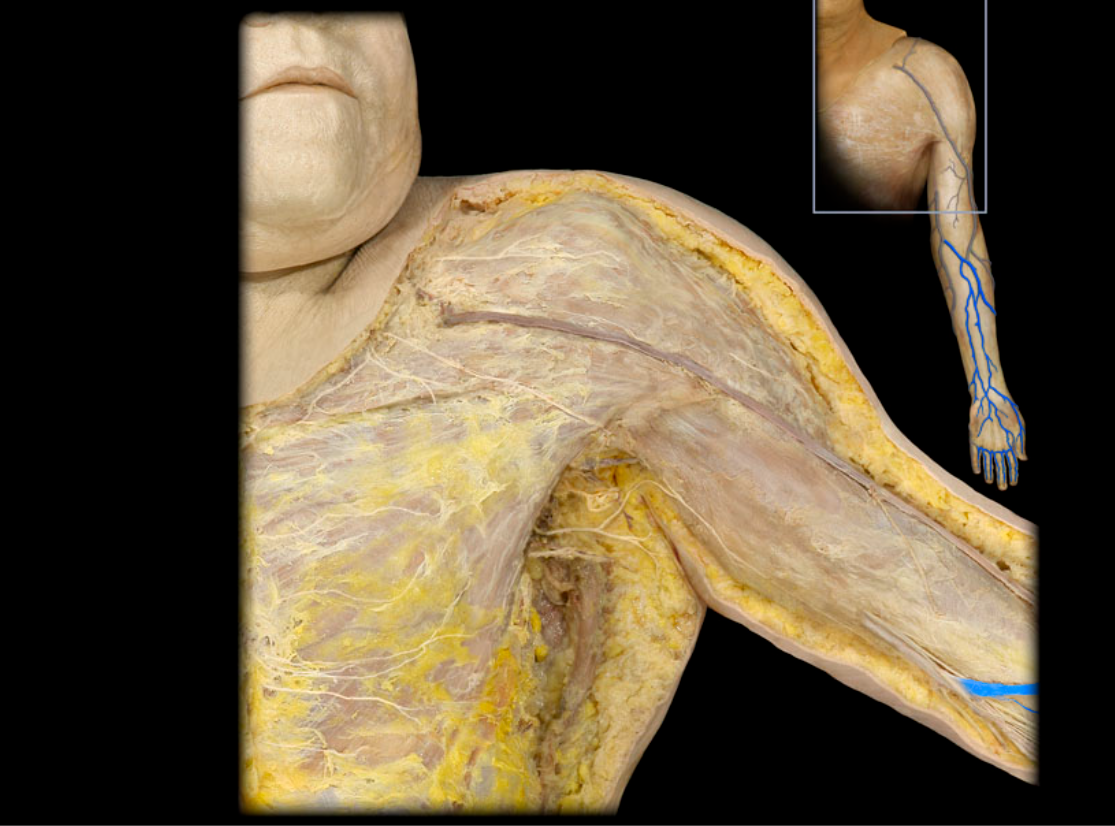

Axillary a.

Basilic v.

Brachial a.

Cephalic v.

Cephalic v. and tributaries

Median cubital v.

Subclavian v.